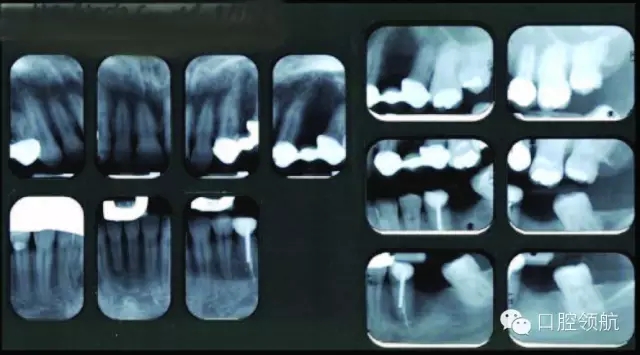

圖3 上頜左側后牙的影像學檢查。

咨詢修復、牙體牙髓及正畸科,制訂詳細的治療計劃。行錐形束CT檢查上頜牙弓,以更好地了解缺損處牙槽嵴的形態(tài)及和上頜竇的鄰接關系(圖4)。

CT顯示牙槽嵴的垂直距離足夠,為更好地植入種植體,尚需有6~7mm的骨寬度。該區(qū)域的最終治療計劃包括:引導骨再生,修復以及咬合重建,包括#4-X-6種植體支持的局部固定義齒。

圖4 (A~C)CT檢查,顯示14號牙(左上頜第一磨牙)的牙槽嵴水平缺損。